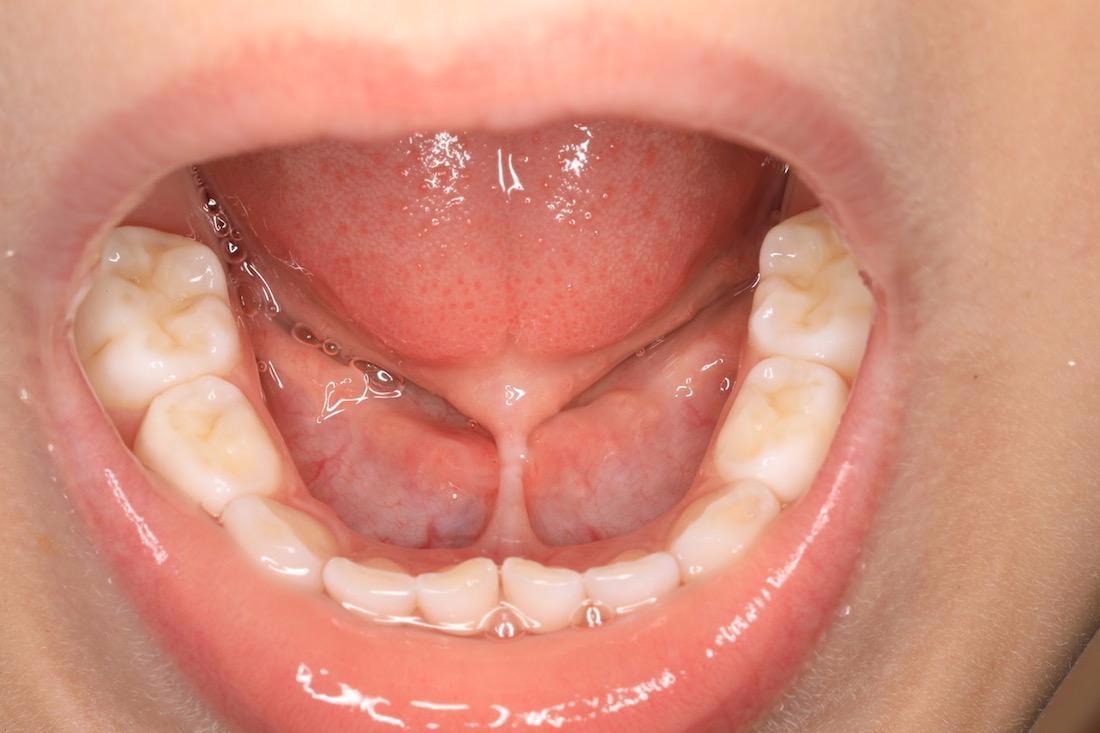

Lip and Tounge Tie treatment was performed on a young patient to help release the tongue and aide in talking and eating comfortably.